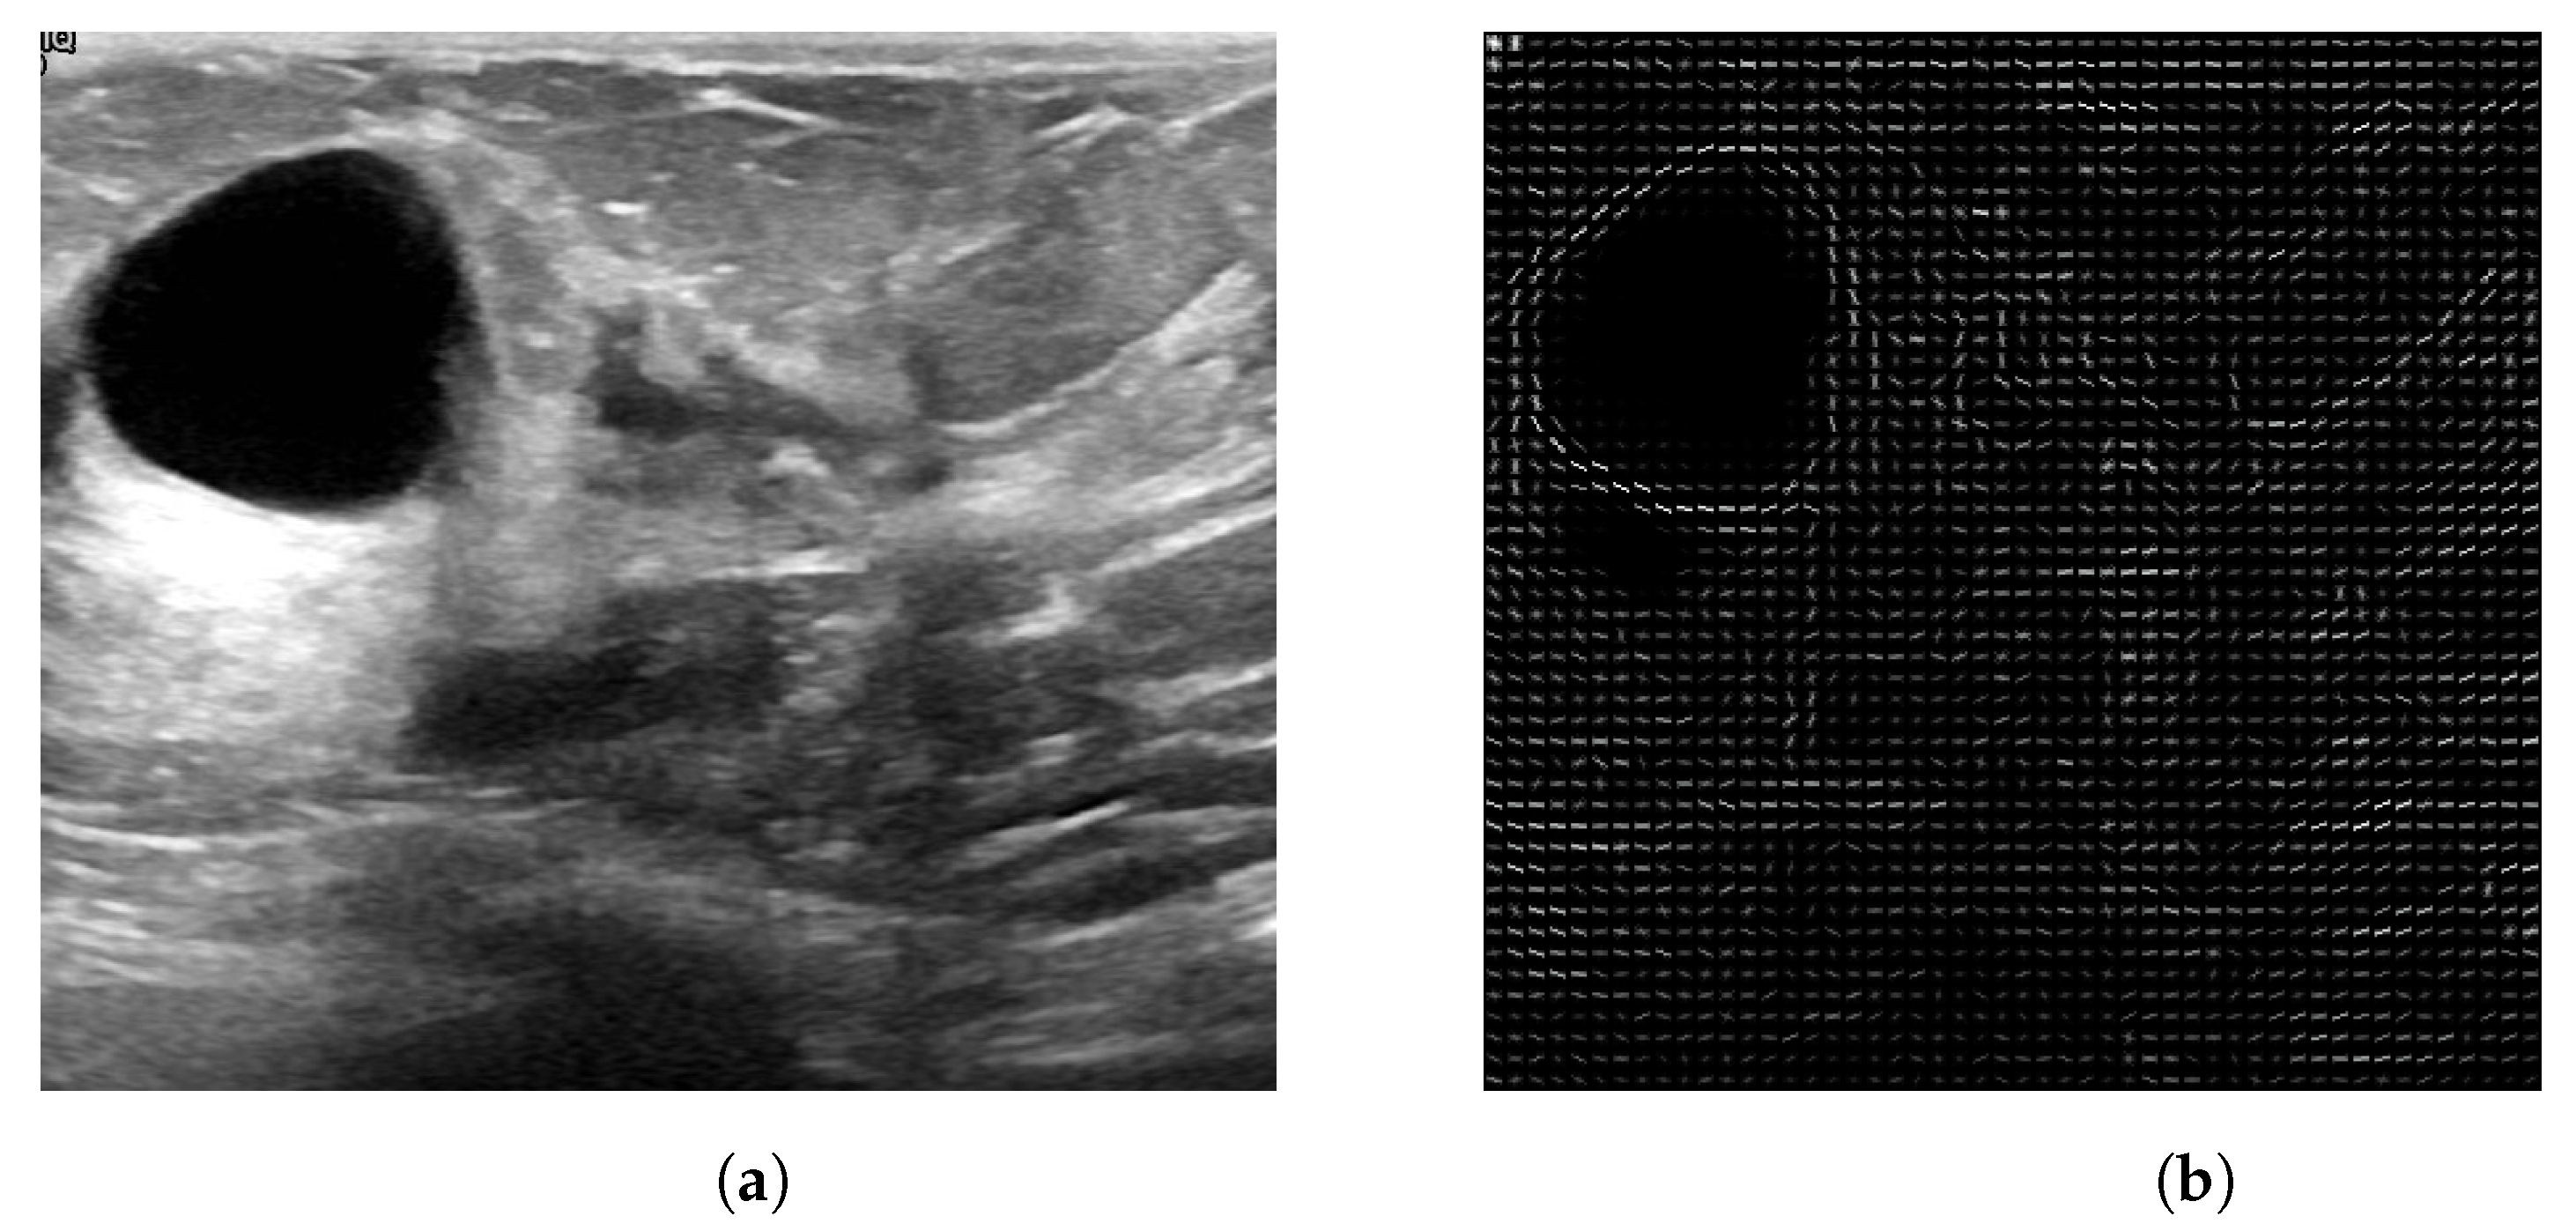

2.1. Databases Used

The Breast Ultrasound Images Dataset (Dataset BUSI) is a dataset that was collected in 2018. The collected data consist of 780 breast US images in PNG format, with size 500 × 500 pixels, including the segmentation masks belonging to 600 patients. Additionally, the images are labeled with one of three classes: normal, benign, and malignant. The database can be obtained online [22]. The mini-DDSM is a current version of the DDSM (Digital Database for Screening Mammography) and is presented in 8-bit JPEG and 16-bit PNG formats. The data are divided into normal, benign, and malignant classes. In addition, the images contain the location of a lesion. The database can be obtained from the following studies and webpage [22,23,24]. Figure 1 and Figure 2 present several examples of benign and malignant lesions from these datasets.

Obtaining the ROI image from US is more difficult due to the noise (speckle) contained and low contrast values, due to the nature of the acquisition process [11]. Moreover, the lesion is visible to the specialist due to their trained eye, so a radiologist manually cropped each image and labeled the ROI.

After calculating the LBP texture features and HOG shape features, a feature vector for each descriptor is obtained. The HOG features describe shape patterns, employing the gradients and their directions to help, for both the US and MG images, in the characterization of the edges (shapes) of a lesion. LBP features characterize the texture of a lesion, since it is different from breast tissue. Therefore, by employing LBP features, we can expose the texture spotlights of the lesions and the pixels that compose them. Figure 10 presents the generated HOG image, where one can see the texture obtained for the lesion.